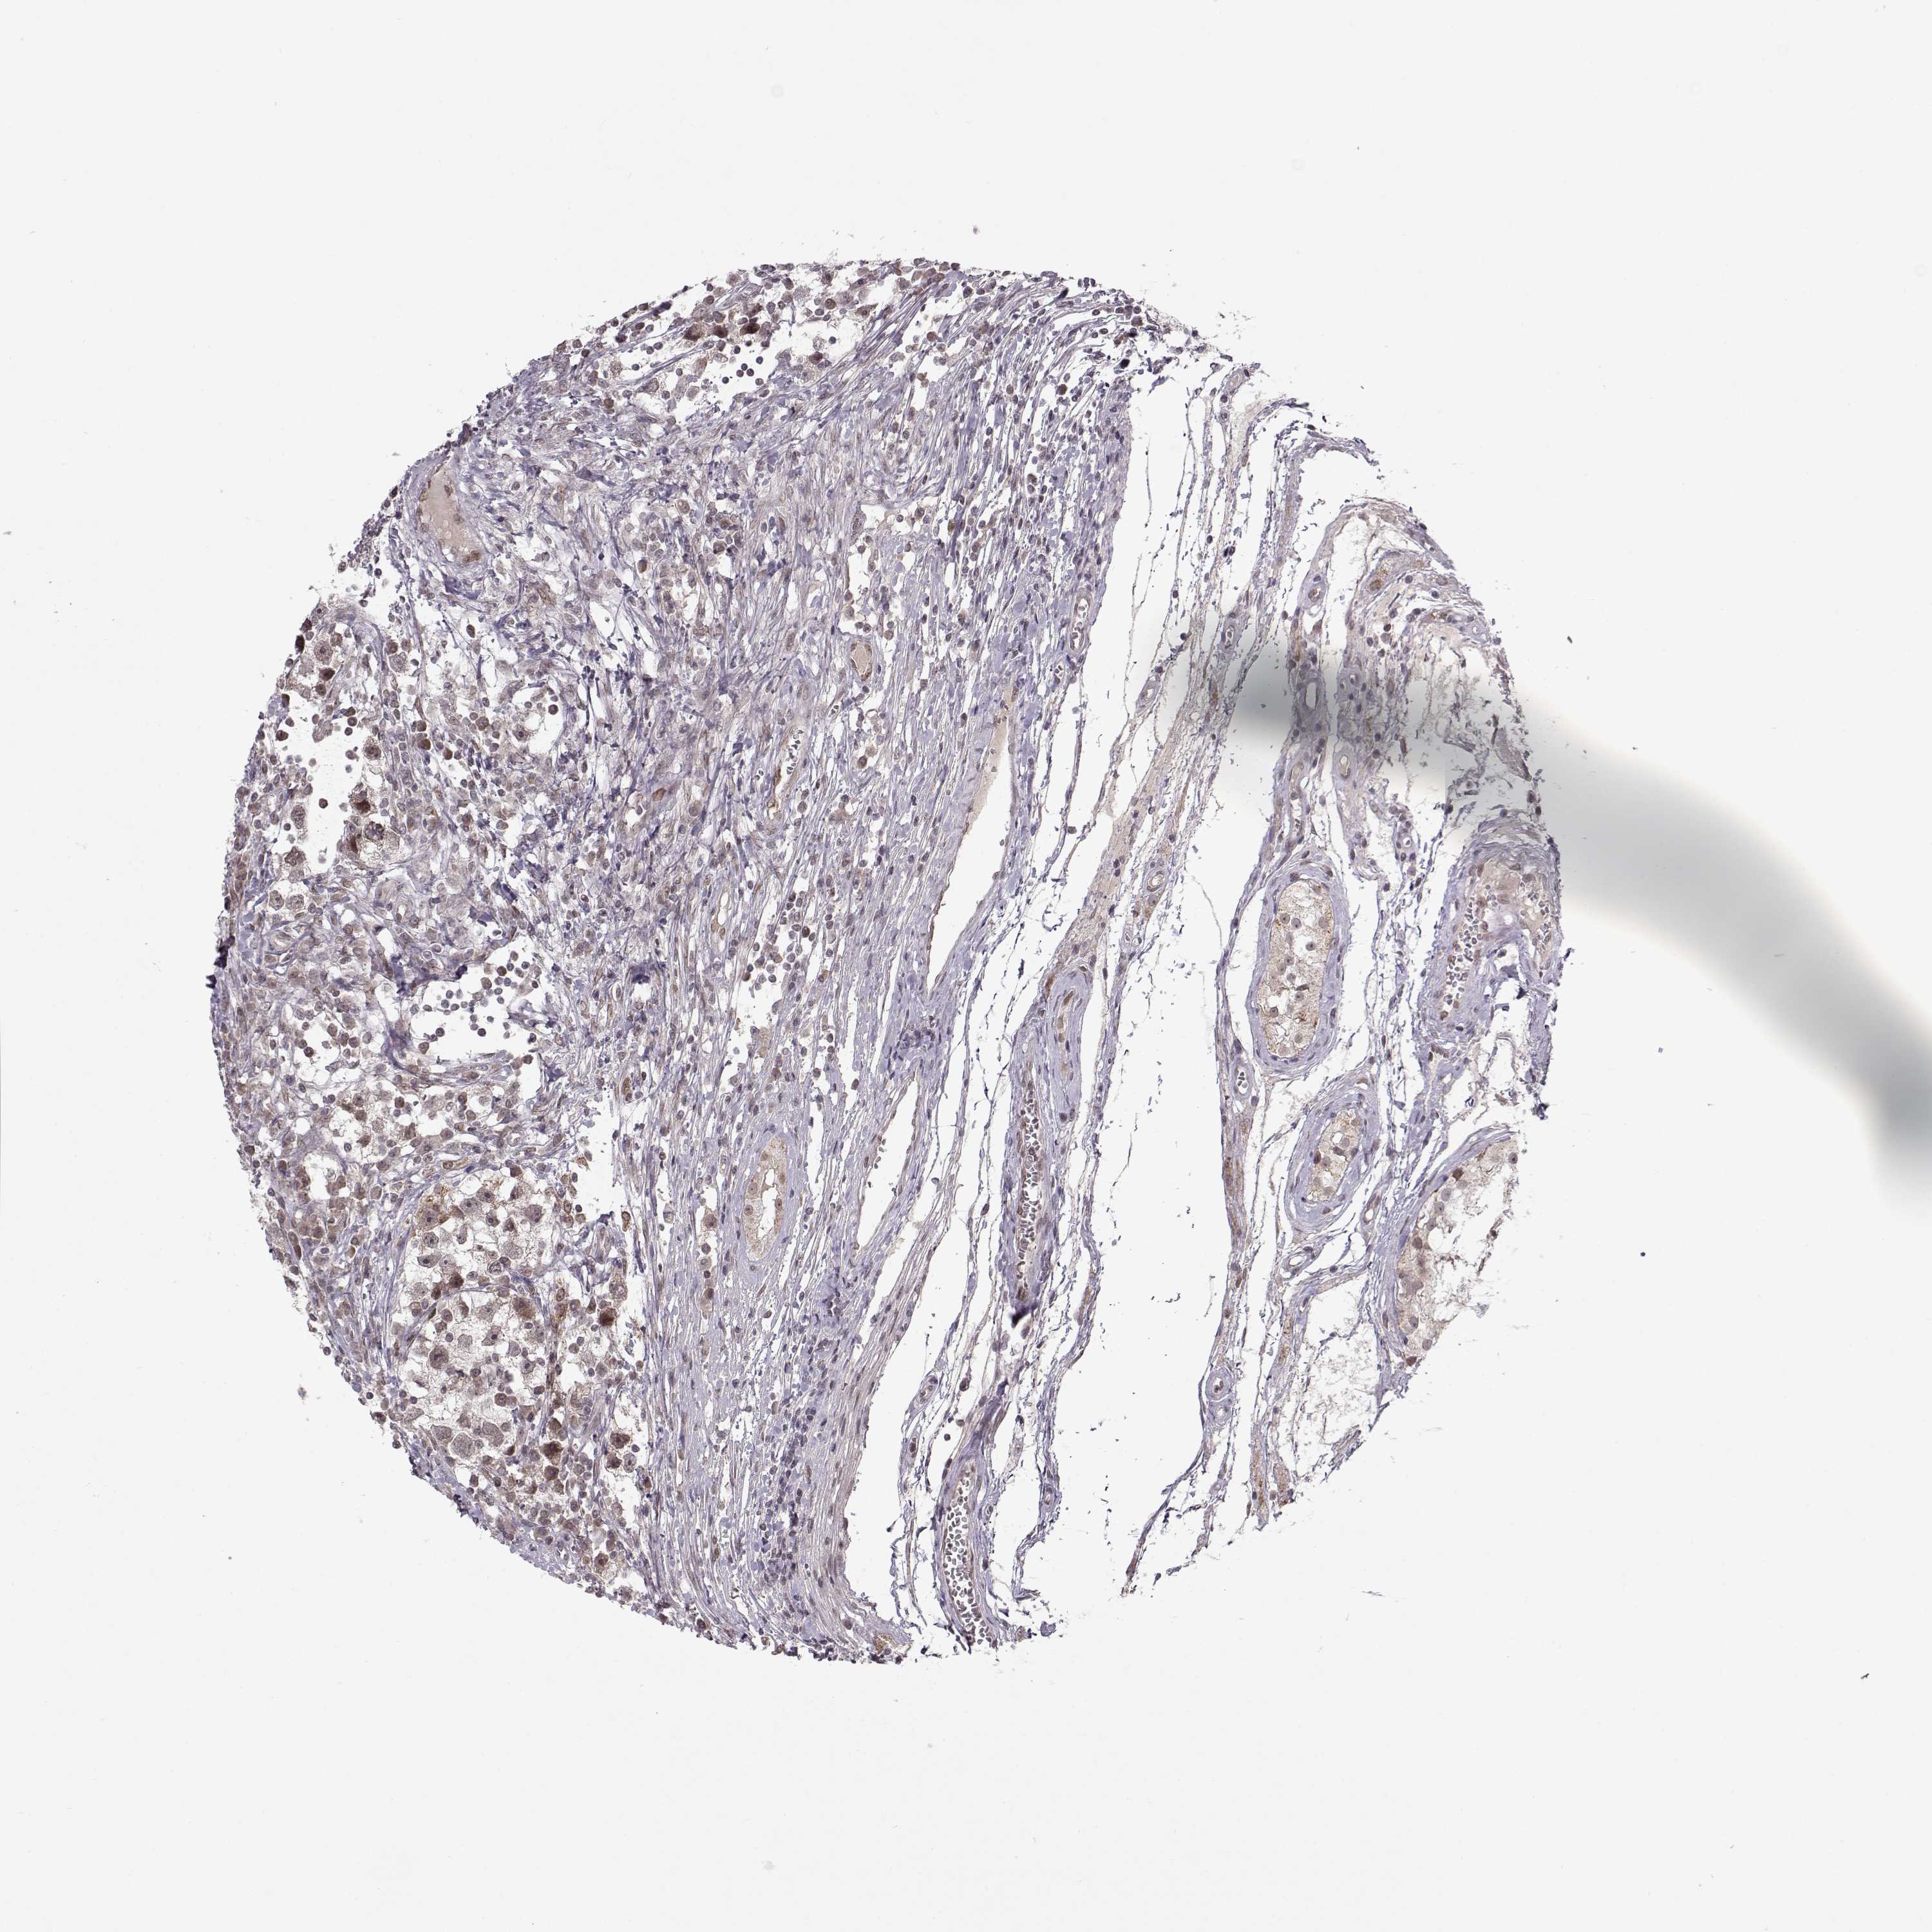

TESTIS CANCER - Protein expressioni

A mouse-over function shows sample information and annotation data. Click on an image to view it in a full screen mode. Samples can be filtered based on level of antibody staining by selecting one or several of the following categories: high, medium, low and not detected. The assay and annotation is described here.

Note that samples used for immunohistochemistry by the Human Protein Atlas do not correspond to samples in the TCGA dataset.

Antibody stainingi

Antibody staining in the annotated cell types in the current human tissue is reported as not detected, low, medium, or high, based on conventional immunohistochemistry profiling in selected tissues. This score is based on the combination of the staining intensity and fraction of stained cells.

Each image is clickable and will lead to virtual microscopy that enables deeper exploration of all samples and also displays staining intensity scores, fraction scores and subcellular localization as well as patient and tissue information for each sample.

Antibody HPA054906

Staining

High

Medium

Low

Not detected

Intensity

Strong

Moderate

Weak

Negative

Quantity

>75%

75%-25%

<25%

None

Location

Nuclear

Cytoplasmic/membranous

Cytoplasmic/membranous,nuclear

Seminoma, NOS

Carcinoma, Embryonal, NOS

Teratoma, malignant, NOS